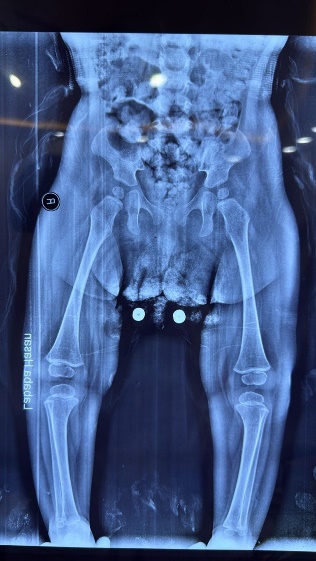

Figure 2: Hands and feet deformities

Short, broad hands and feet with clenched fingers and bilateral clubfoot, consistent with skeletal anomalies described in HPMR

Skeletal: Short broad hands/feet, clenched fists, bilateral clubfoot.

Figure 11: Skeletal deformities of the upper and lower limbs

Photographs showing short, broad hands with clenched fingers (upper image) and bilateral clubfoot deformities (lower image), consistent with skeletal abnormalities described in HPMRS.